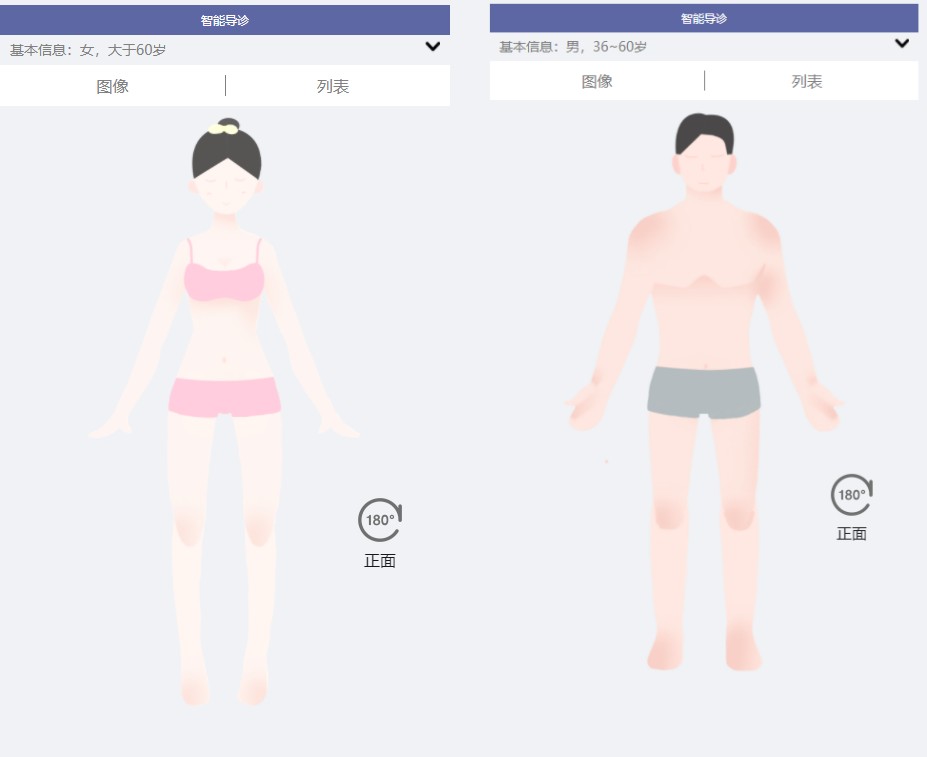

四、智慧医院3D智能导诊系统源码 H5端和微信小程序

智能导诊界面,可以根据性别来选择人体结构图,有成年男性、成年女性、男童、女童。页面会显示男性或女性的身体结构图,可切换正面/背面。